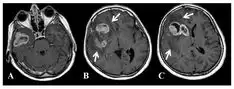

교모세포종의 진단은 주로 고해상도의 영상 진단 도구인 MRI 또는 CT를 통해 이루어집니다.

이러한 검사를 통해 종양의 위치, 크기 및 주변 조직과의 관계를 정확히 평가할 수 있습니다.

또한, 최종적인 진단을 위해서는 조직 검사가 필수적으로 수행됩니다.